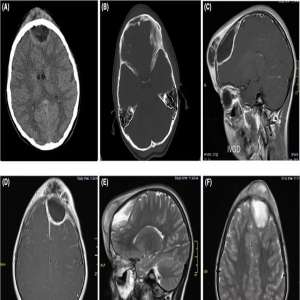

بثرة على جبين فتاة تتحول إلى ورم مميت